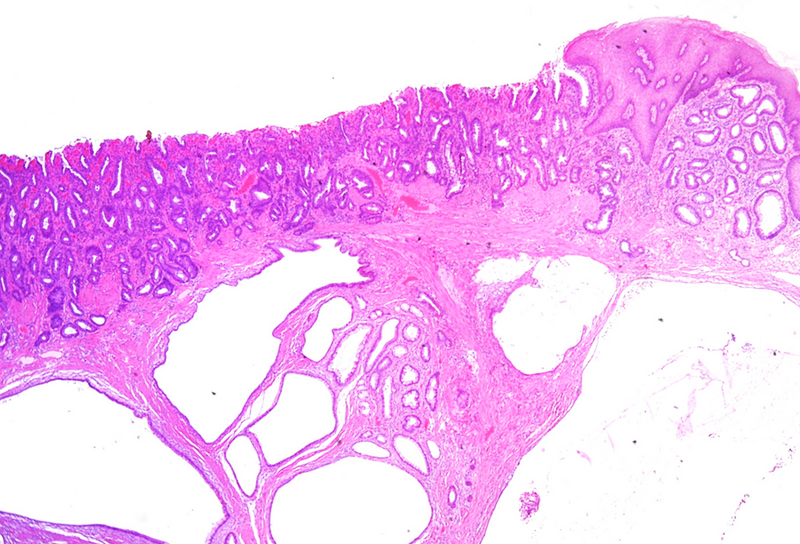

Polypoid lesion at the anorectal junction in a 47 year-old male.

Proctitis cystica profunda.

Microscopically, one specimen disclosed cystically dilated structures of variable size underneath regular colonic  / anal mucosa (Panels A-B). The cysts are filled with mucin, and the epithelial lining is of intestinal type, showing reactive changes, yet no dysplasia in the presence of mixed unspecific inflammation (Panels C-D).

Histologically, it is characterized by the presence of either localised, segmental, or diffuse mucus-filled cysts of the deep submucosa and even muscularis propria. Size of the cysts may differ, depending on localisation and diffuse morphology, lesions can measure up to even 2 cm. The lining epithelium lacks atypia, with only minor nuclear irregularities in case of secondary inflammatory changes. The overlying mucosa is intact. Surrounding areas may contain fibrosis and hemosiderin laden macrophages. The cysts may rupture causing mucin dissemination into the surrounding tissue, potentially followed by degenerative calcification. Differential diagnosis mainly includes mucinous adenocarcinoma, which may be identified by nuclear dysplasia and/or desmoplastic response.